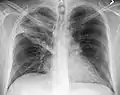

A black and white X-ray picture showing a triangle white area on the left side. A circle highlights the area.

A chest X-ray showing a very prominent wedge-shape bacterial pneumonia in the right lung